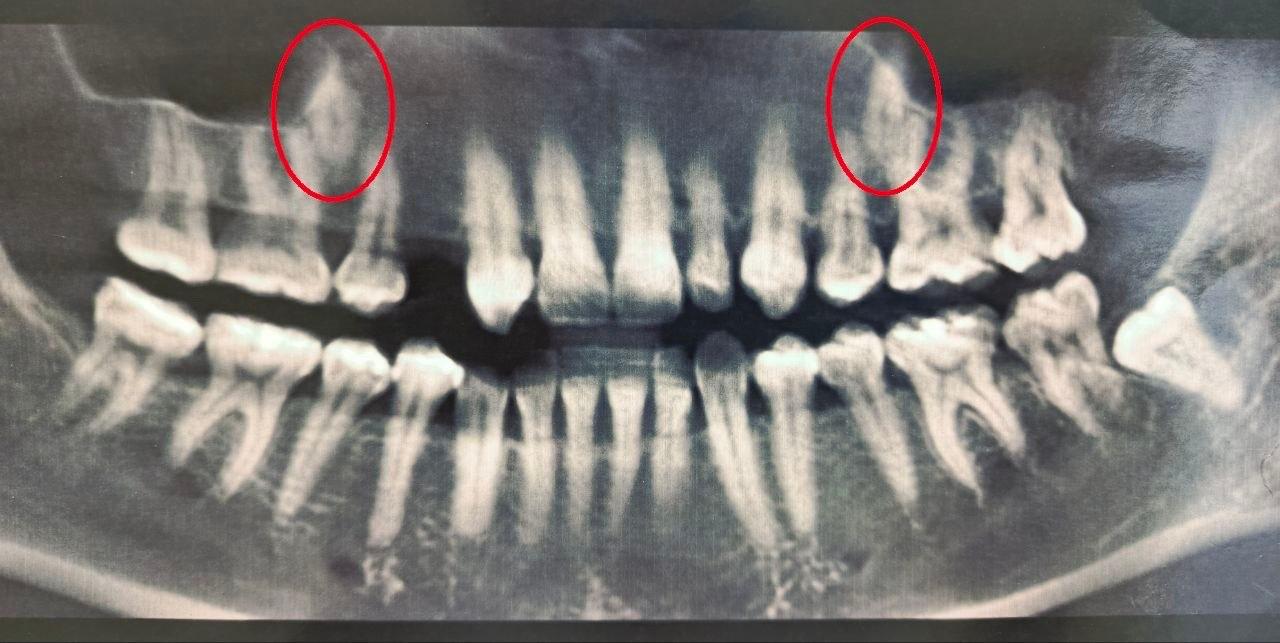

В 2023 году врачи выяснили, что один из зубов у женщины полностью отсутствовал, а второй был намного меньше нормы. Тогда врачи решили вмешаться и переместить непрорезавшиеся зубы в ряд.

Стоматологи установили пациентке брекеты, которые та носила на протяжении полутора лет, создавая место для новых зубов. После этого врачи хирургически раскрыли коронки непрорезавшихся зубов и зафиксировали ортодонтические кнопки для их вытяжения. На данный момент благодаря специальному оборудованию один из зубов полностью вышел из костной ткани, а второй успешно прорезается.